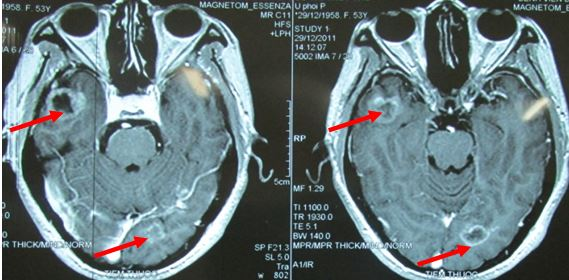

- Chụp MRI sọ não

Hình 2: hình ảnh chụp MRI sọ não cho thấy di căn não đa ổ

Hình 8: U di căn não đa ổ trước điều trị

Hình 9: tổn thương não tiêu biến hoàn toàn, lâm sàng hoàn toàn bình thường